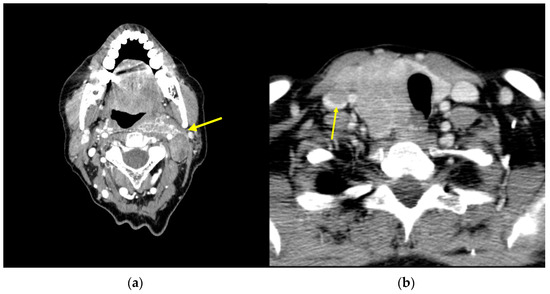

4. Neck Recurrences